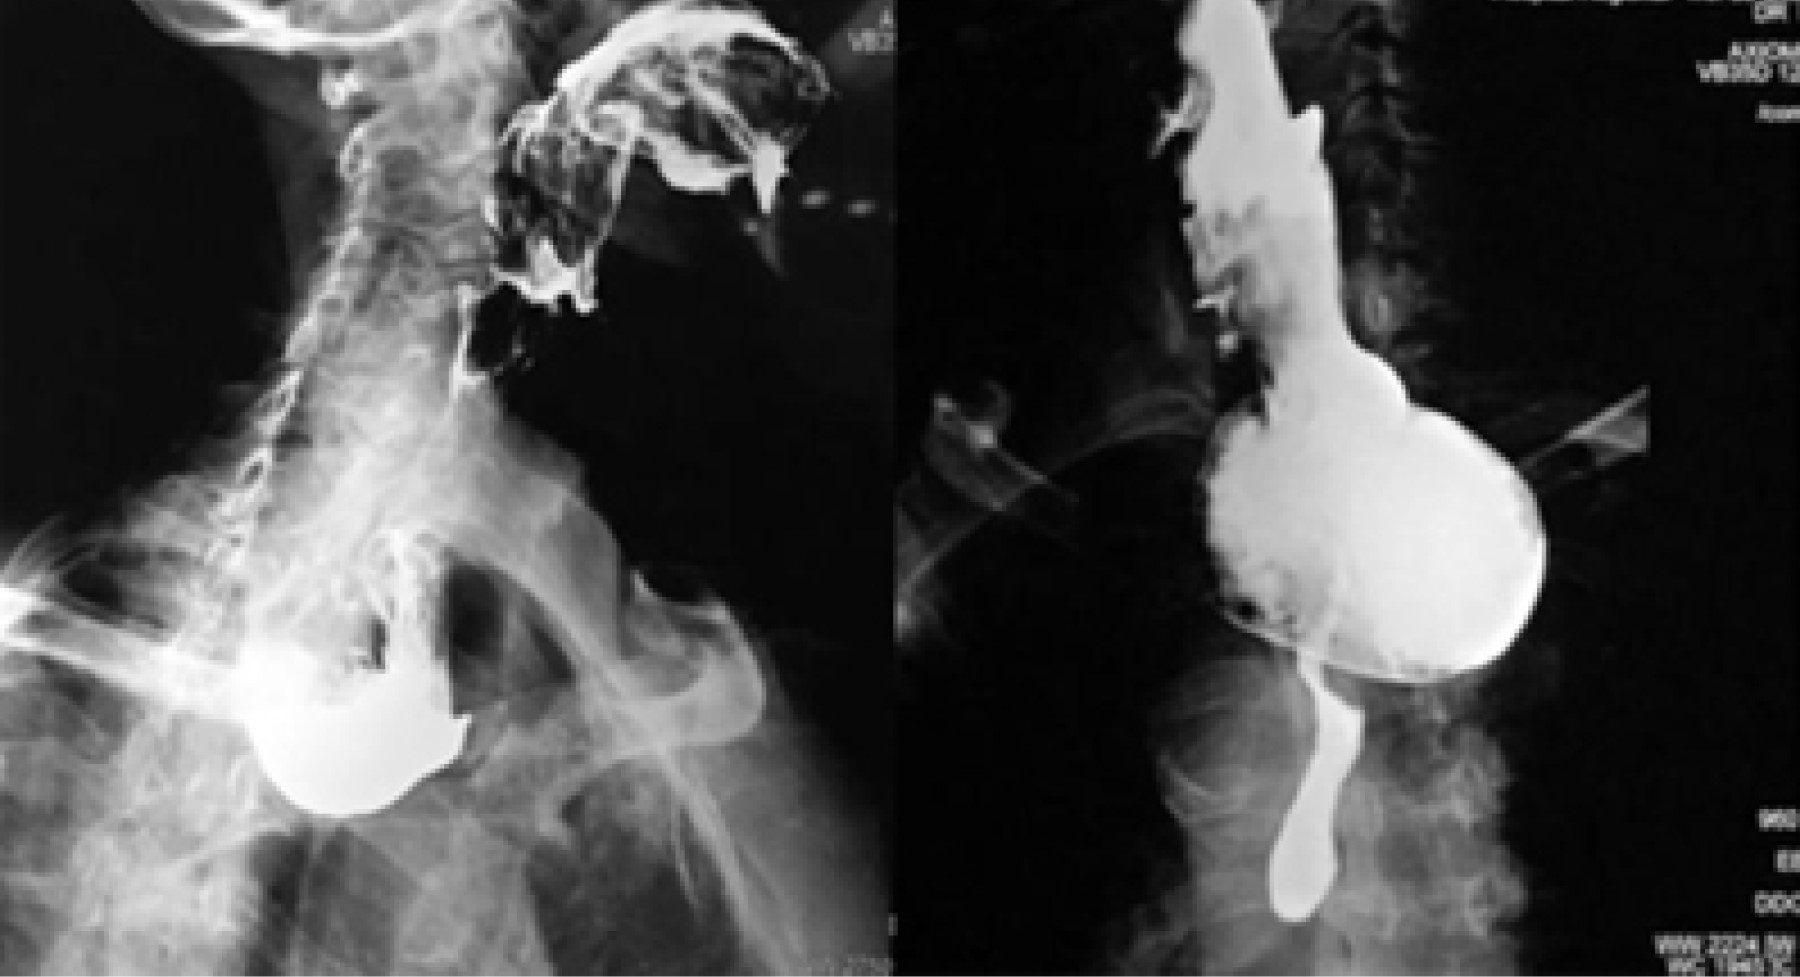

A todos los pacientes se les tomaron datos clínicos demográficos, tales como: edad, sexo, tiempo de evolución de los síntomas y síntomas predominantes, características del divertículo, remisión de los síntomas y necesidad de reintervención. El diagnóstico de divertículo de Zenker se realizó por medio de estudio radiológico de contraste (esofagograma con medio de contraste baritado) y endoscópico, con lo cual se confirmaba el diagnóstico y se calculaba el tamaño del divertículo (Figura 1).

Figura 1